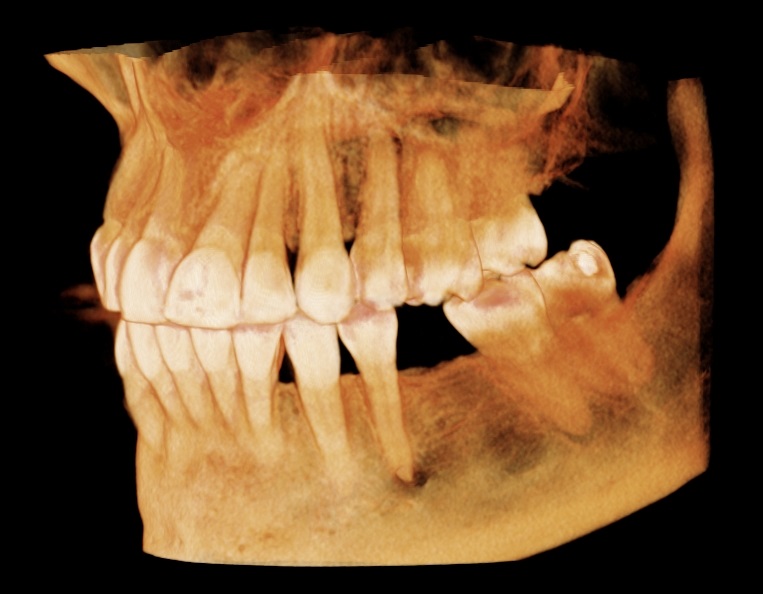

Conventional intra-oral radiography provides clinicians with cost-effective, high-resolution imaging that continues to be the front-line method for dental imaging. However, it is clear that there are many specific situations where the 3-D images produced by CBCT facilitates diagnosis and influences treatment. The usefulness of the CBCT cannot be disputed. It is a valuable task-specific imaging modality, producing minimal radiation exposure to the patient and providing maximal information to the clinician.